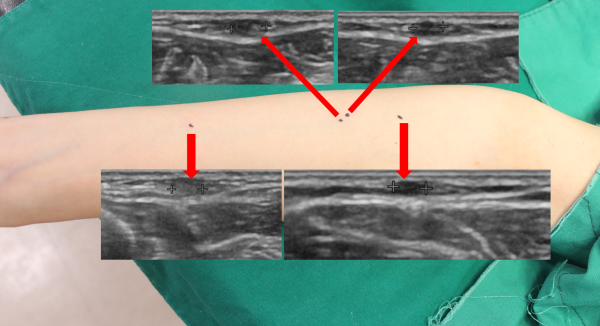

정확한 혹의 양상, 크기, 깊이, 그리고 주변에 혈관이 지나가는지 등을 확인하기 위해 초음파 검사를 시행하였습니다.

초음파상 크기는 0.3~0.5cm 크기로 측정되었으며 피부 바로 아래에 위치해있었고 양상으로 보았을때 다발성 피지낭종 (Steatocytoma multiplex)로 판단되었습니다.